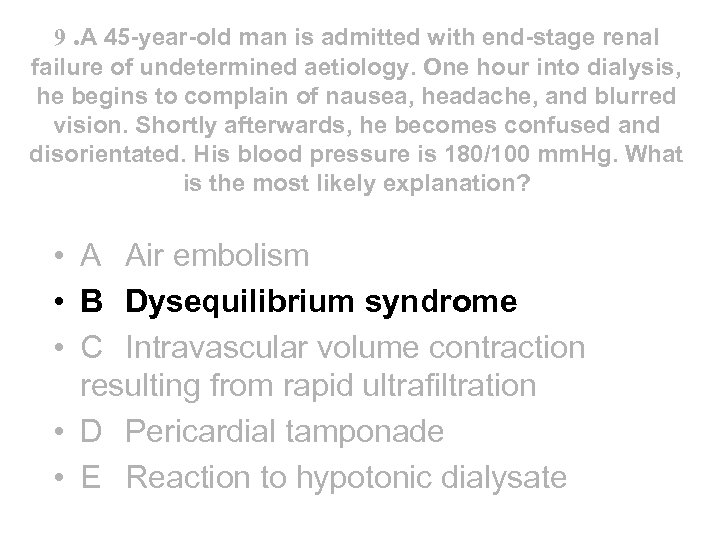

Reflux nephropathy • Treatment • - RCTs have shown equal efficacy of continuous antibiotics until puberty and ureteric reimplantation in children with reflux and UTI - reimplantation now less common than before • - prophylactic antibiotics for asymptomatic infection now no longer recommended after puberty • - only patients with serious recurrent UTI or pyonephrosis require nephrectomy before transplantation (bilateral nephrectomy not routine) • Outcome • - combination of reflux and UTI usually required to cause scarring and CRF • - but new scars rarely develop after 8 yrs of age • - progressive loss of renal function, invariably assoc with HT and proteinuria, can occur in absence of both UTI and reflux if GFR<50 ml/min • - CRF not caused by recurrent acute pyelonephritis - UTI present in a minority of adults • - accounts for ~ 20% cases ESRD requiring dialysis (not 50%)

Reflux nephropathy • Treatment • - RCTs have shown equal efficacy of continuous antibiotics until puberty and ureteric reimplantation in children with reflux and UTI - reimplantation now less common than before • - prophylactic antibiotics for asymptomatic infection now no longer recommended after puberty • - only patients with serious recurrent UTI or pyonephrosis require nephrectomy before transplantation (bilateral nephrectomy not routine) • Outcome • - combination of reflux and UTI usually required to cause scarring and CRF • - but new scars rarely develop after 8 yrs of age • - progressive loss of renal function, invariably assoc with HT and proteinuria, can occur in absence of both UTI and reflux if GFR<50 ml/min • - CRF not caused by recurrent acute pyelonephritis - UTI present in a minority of adults • - accounts for ~ 20% cases ESRD requiring dialysis (not 50%)

18 With regard to lupus nephritis: • A It may present with a rapidly progressive glomerulonephritis • B It may present with histological changes similar to diabetic nephropathy • C It should be treated with oral steroids alone when associated with a membranous histology • D It should only be treated with cytotoxic agents when serum creatinine > 120 mol/l • E Frequently complicates drug induced SLE

18 With regard to lupus nephritis: • A It may present with a rapidly progressive glomerulonephritis • B It may present with histological changes similar to diabetic nephropathy • C It should be treated with oral steroids alone when associated with a membranous histology • D It should only be treated with cytotoxic agents when serum creatinine > 120 mol/l • E Frequently complicates drug induced SLE